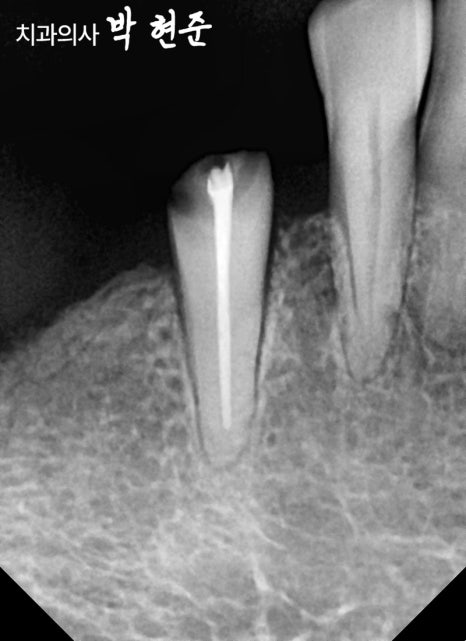

사진 상으로는 비어있는 구치부의

치조골 높이가 양호한 것으로 보이기 때문에

태평역임플란트 식립이 가능할 것으로 보여집니다.

파절된 이는 뽑고

픽스처를 심어 재건할 수 있을 것으로 보여집니다.